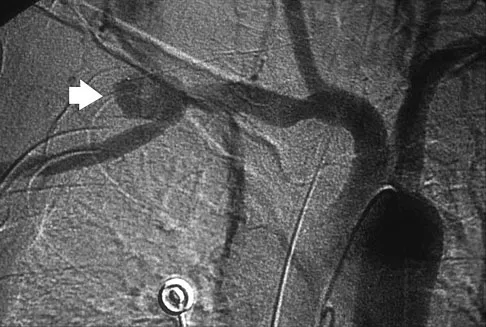

A previously healthy 65-year-old woman has a closed fracture of the right clavicle after falling down the basement stairs. Examination reveals good capillary refill in the digits of her right hand. Radial and ulnar pulses are 1+ at the right wrist compared with 2+ on the opposite side. In the arteriogram shown in Figure 36, the arrow is pointing at which of the following arteries?

The axillary artery commences at the first rib as a direct continuation of the subclavian artery and becomes the brachial artery at the lower border of the teres major. The arteriogram reveals a nonfilling defect in the third portion of the artery just distal to the subscapular artery. The complex arterial collateral circulation in this region often permits distal perfusion of the extremity despite injury.